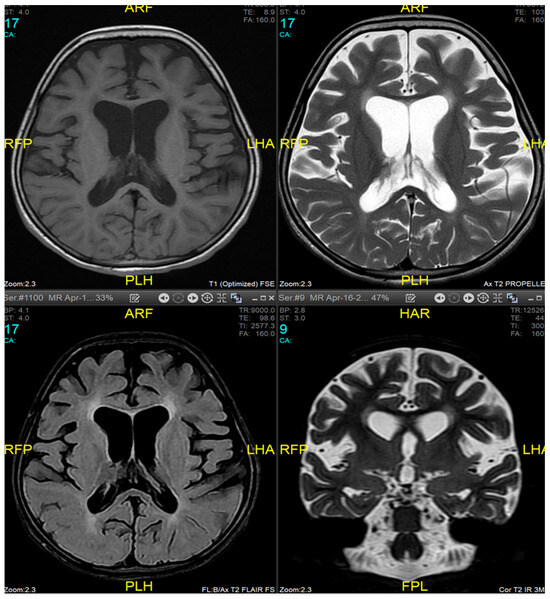

2. Case Presentation